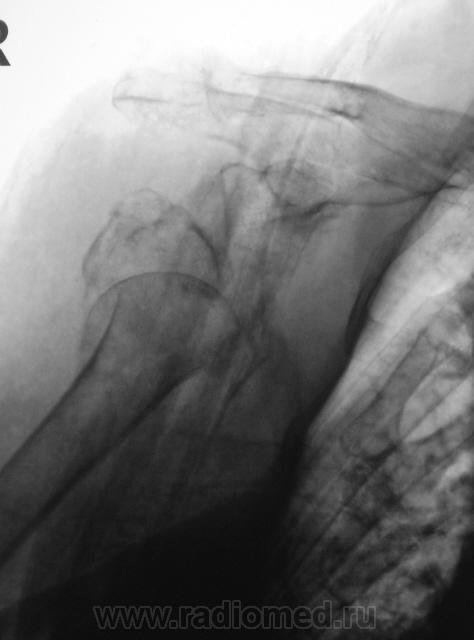

Пол пациента: Женский пол Тип патологии: Травма Область исследования: Скелетно-мышечная система Методы исследования: Rg Мы, ранее демонстрировали и "первичный" снимок и снимок после наложения "гипсовой повязки", вот он... https://radiomed.ru/sites/default/files/styles/case_slider_image/public/user/12/22.Pervyy.P4290004a.jpg?itok=J8w9QKuH ID:3524 Пт, 30/04/2010 - 23:44 #1 Катенёв Валенти... Не на сайте Был на сайте: 7 лет 3 недели назад Зарегистрирован: 22.03.2008 - 22:15 Публикации: 54876 Конечно, в протоколе все было подробнейшим образом описано. Какое же было удивление, когда через месяц, "гипсовая повязка" была снята... и пациентка была направлена на "контроль" с целью подтверждения "консолидации перелома". Приложения: Сб, 01/05/2010 - 10:00 #2 Vikkur Не на сайте Был на сайте: 4 года 8 месяцев назад Зарегистрирован: 24.09.2009 - 14:34 Публикации: 1749 НО комент..."Вечно эти рентгенологи понапишут" Виктор. Чт, 13/05/2010 - 16:49 #3 Сан Саныч Не на сайте Был на сайте: 15 лет 6 месяцев назад Зарегистрирован: 23.04.2010 - 20:23 Публикации: 73 !!!!!!!!!!!!!!!!!!!!!!

Конечно, в протоколе все было подробнейшим образом описано.

Какое же было удивление, когда через месяц, "гипсовая повязка" была снята... и пациентка была направлена на "контроль" с целью подтверждения "консолидации перелома".

НО комент..."Вечно эти рентгенологи понапишут"